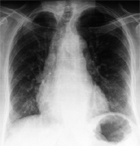

Les radiologies pulmonaires de 934 femmes de plus de 60 ans hospitalisées pour diverses raisons ont été relues. Une fracture vertébrale (FV) était présente chez 130 patientes.

La FV était signalée dans le Compte Rendu (CR) radiologique dans 52% des 130 patientes, signalée dans la conclusion du CR dans 23%, une ostéoporose fracturaire était signalée dans 17% dans le CR médical et une ostéoporose a été traitée dans 7%.